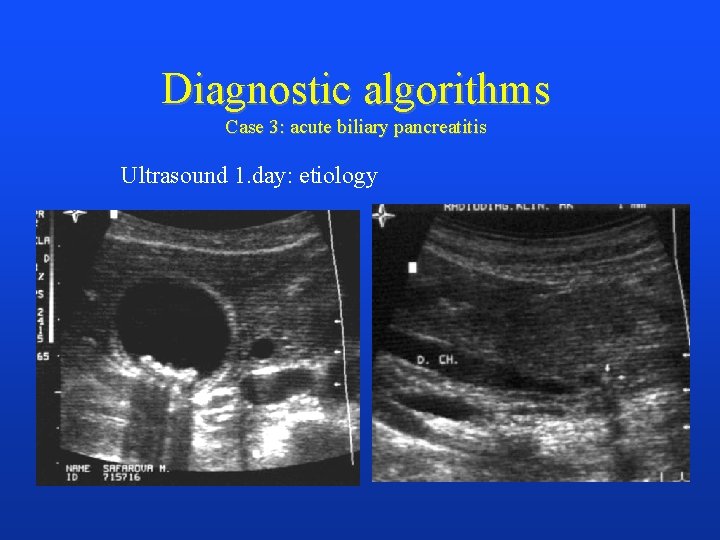

Diagnostic algorithms Case 3: acute biliary pancreatitis Ultrasound 1. day: etiology

ERCP 1. day, papilotomy: treatment CT with CA, 4. day: staging AP